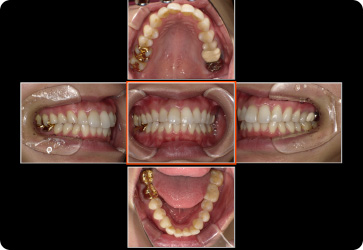

歯周病レントゲン検査・口腔内写真

歯を支えている顎の骨(歯槽骨)の損失具合がわかります。